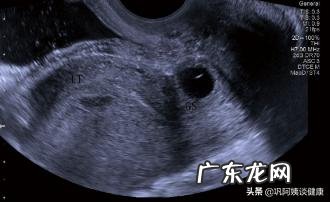

超声诊断:子宫瘢痕妊娠可能(子宫切口处见胚囊27mm×20mm×15mm)

诊断要点:①妊娠囊位于子宫下段剖宫产瘢痕处:②子宫前壁肌层连续性中段 , 或者子宫前壁肌层变薄:③cdfi示妊娠囊周边见滋养层低阻血流 。